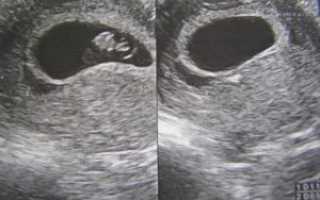

УЗИ на 9 неделе беременности

На УЗИ плода на 9 неделе определяется толщина плаценты и общее состояние пуповины. При помощи допплера, будущая мама может отметить частоту сердечных сокращений малыша. Хотя многие внутренние органы уже достаточно развиты, это не всегда можно увидеть на УЗИ на 9 неделе.

Внутренние органы крохи еще могут выступать в виде пупочной грыжи, но нет повода для беспокойства, ведь это совершенно нормальное явление.

Определить пол будущего ребенка на УЗИ ещё нельзя, однако, существуют другие способы узнать пол своего малыша. О достоверных способах мы говорили в этой статье.

На девятой акушерской неделе беременности ультразвуковое обследование позволяет услышать биение сердечка ребеночка. Помните, что акушерский срок немного отличается от эмбрионального возраста плода. Это примерно 1-2 недели.

В норме сердце плода бьется 140-160 ударов в секунду. При обследовании частота может повышаться. Ведь это стресс, и малыш волнуется. Также в такой ситуации может сокращаться матка.

Но диагноз «гипертонус» ставится только в том случае, если сокращение стенок матки происходят постоянно, а не во время УЗИ.

В данный срок специалист УЗИ оценивает состояние жёлтого тела, которое вырабатывает гормон прогестерон. Сейчас недостаток этого вещества крайне опасен и может привести к прерыванию беременности.

Ультразвуковоеисследование плода на сроке девятаяакушерская неделя беременности (перваянеделя третьего акушерского месяца)проводят только при специальныхпоказаниях. В данное время обычноврач-гинеколог это исследование неназначает.

Половые признаки внутриутробногомалыша разглядеть на фото9 недели беременностипрактически не представляется возможным.Однако можно увидеть, одноплодная илимногоплодная беременность у будущеймамы. Данный методисследования сейчас малоинформативен.

Плановое ультразвуковое исследованиев женской консультации обычно проводятв конце первого триместра беременности,на сроке одиннадцатая или двенадцатаянеделя.